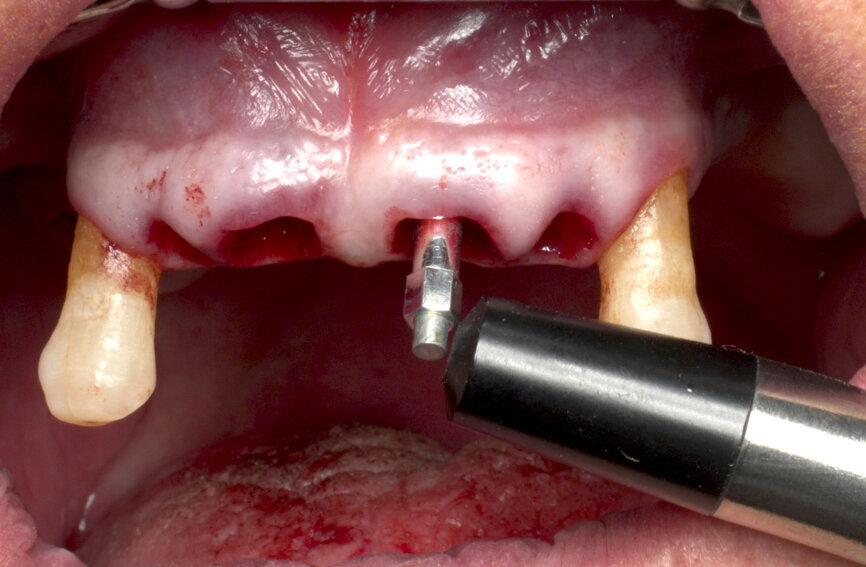

Furthermore, undersized drilling with continuous bone density assessment according to the operator’s own experience is mandatory to achieve the highest insertion torque, taking account of the biological bone situation and the mechanical properties of Roxolid. In this case, six implants (Straumann BLT, Regular Neck, Roxolid, SLActive, four of ⌀ 4.1 mm and two of ⌀ 4.8 mm) were placed with the handpiece at 45 N cm, with a final manual setting and monitoring of the insertion torque (Figs. 5 & 6). Careful orientation of the Loxim orientation marks is mandatory to maintain the desired parallelism of the SRA prosthetic screws.

After final implant seating, BLT Type 54 SmartPegs from Osstell were placed on each implant, and the ISQ level was measured and recorded at implant connection level. Values between 75 and 85 out of 100 were obtained, confirming the immediate loading possibility on all the implants (Figs. 7 & 8).